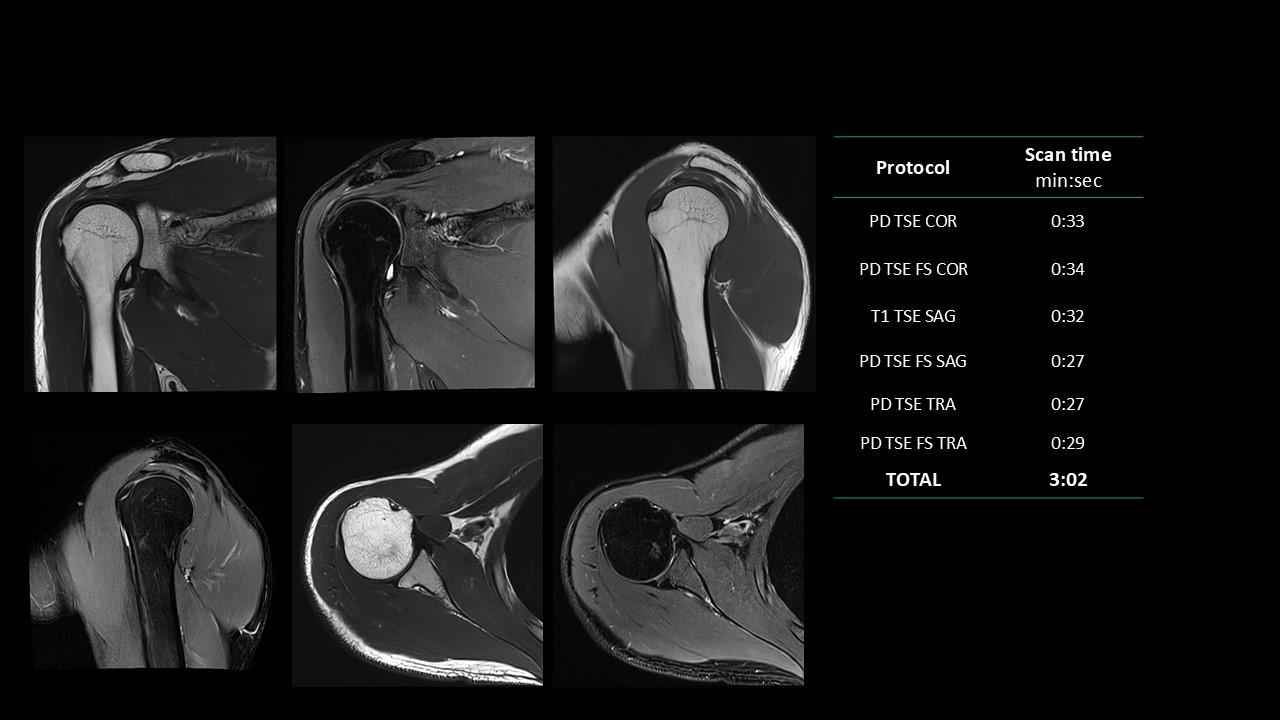

The Deep Resolve protocols are a set of advanced 3T MR imaging protocols designed to achieve high-quality diagnostic imaging with significantly reduced acquisition times.

Enabled by Deep Resolve, the AI-powered image reconstruction technology, these protocols deliver high-quality scans in approximately three minutes across a wide range of anatomical regions.

Developed and meticulously evaluated by Dr. Seong-ho Lee of Leaders Radiology Hospital in Seoul, Korea, the protocols integrate deep learning technology to enhance imaging efficiency while maintaining diagnostic detail.

By reducing scan duration, they improve workflow efficiency and patient experience without compromising image quality.